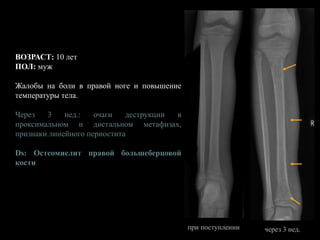

ВОЗРАСТ: 10 лет

ПОЛ: муж

Жалобы на боли в правой ноге и повышение

температуры тела.

Через 3 нед.: очаги деструкции в

проксимальном и дистальном метафизах,

признаки линейного периостита

Ds: Остеомиелит правой большеберцовой

кости

при поступлении через 3 нед.